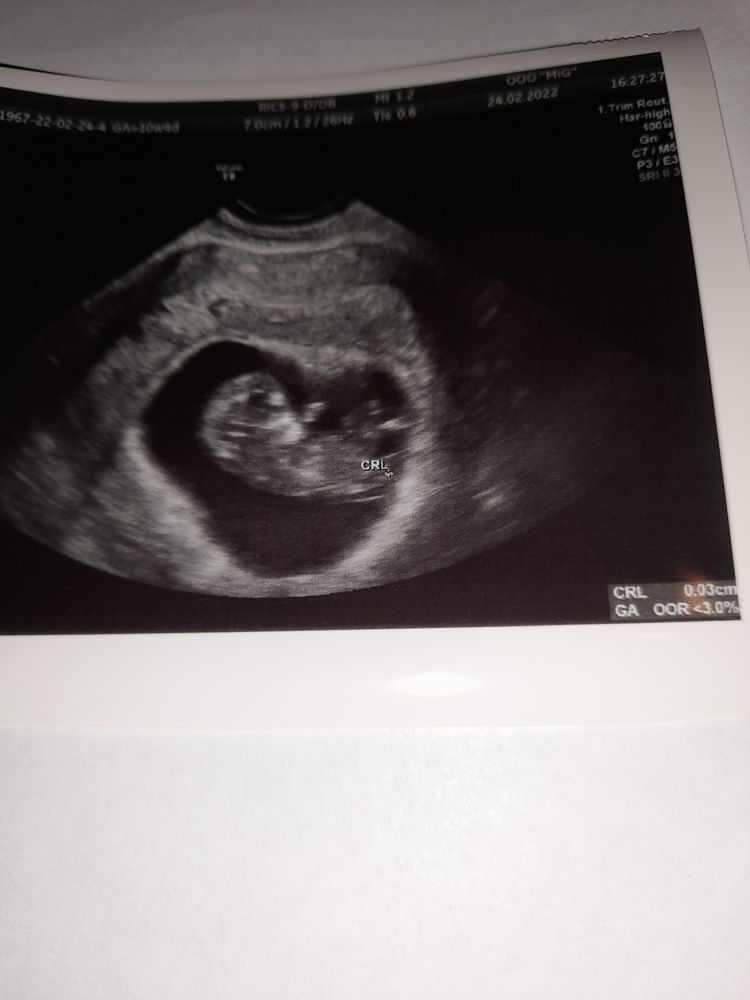

какой большущий!🥳🙌🏼 пусть растет малышок🥰💋 какой ктр сейчас у вас?

Daria, намерили 33 соотв. 10+1. У моей намерилось бы все 40😁я заметила погрешность у них😄в общем 3 дня разница🥰

Christina, я думаю больше у вас🤗 я в пятницу на УЗИ была, намерили 27 мм